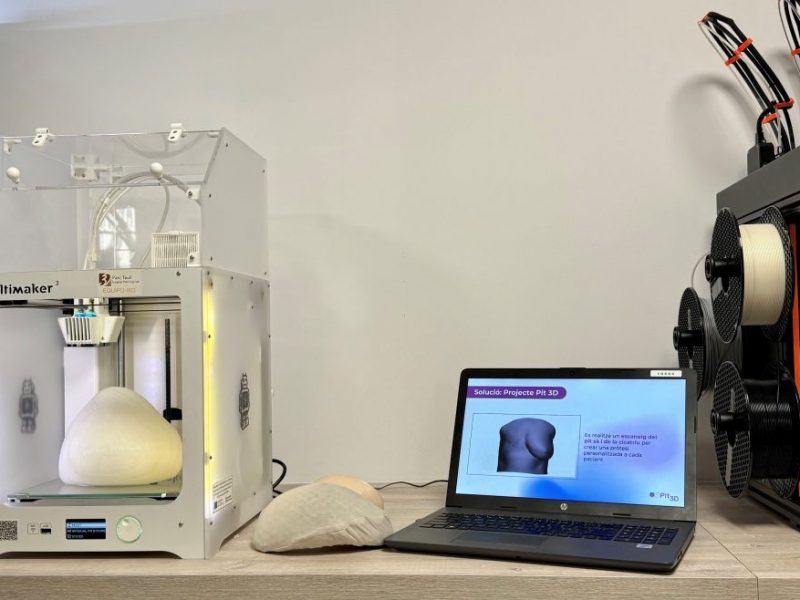

Aquesta solució ha consistit en un conjunt d’eines i programes informàtics per al disseny, planificació i impressió 3D no aplicades fins ara a l’assistència sanitària, que funcionen de manera coordinada per agilitzar i millorar la qualitat dels processos quirúrgics. En concret, la solució incorpora: impressores 3D que amplien la capacitat productiva de l’I3PT i redueixen els temps en la fase de disseny; eines d’escaneig 3D per al mesurament de precisió preoperatòria de forma no invasiva que permeten l’avaluació de tot el cos per a optimitzar la biomecànica personalitzada, substituint així en algunes ocasions el TAC; i programari per a monitorar i realitzar un seguiment de principi a fi dels processos de fabricació i quirúrgics, garantint la qualitat necessària per a produir una pròtesi biomecànica personalitzada.

Planificació quirúrgica virtual per artroplàstia de maluc (foto superior) i espatlla (foto inferior)